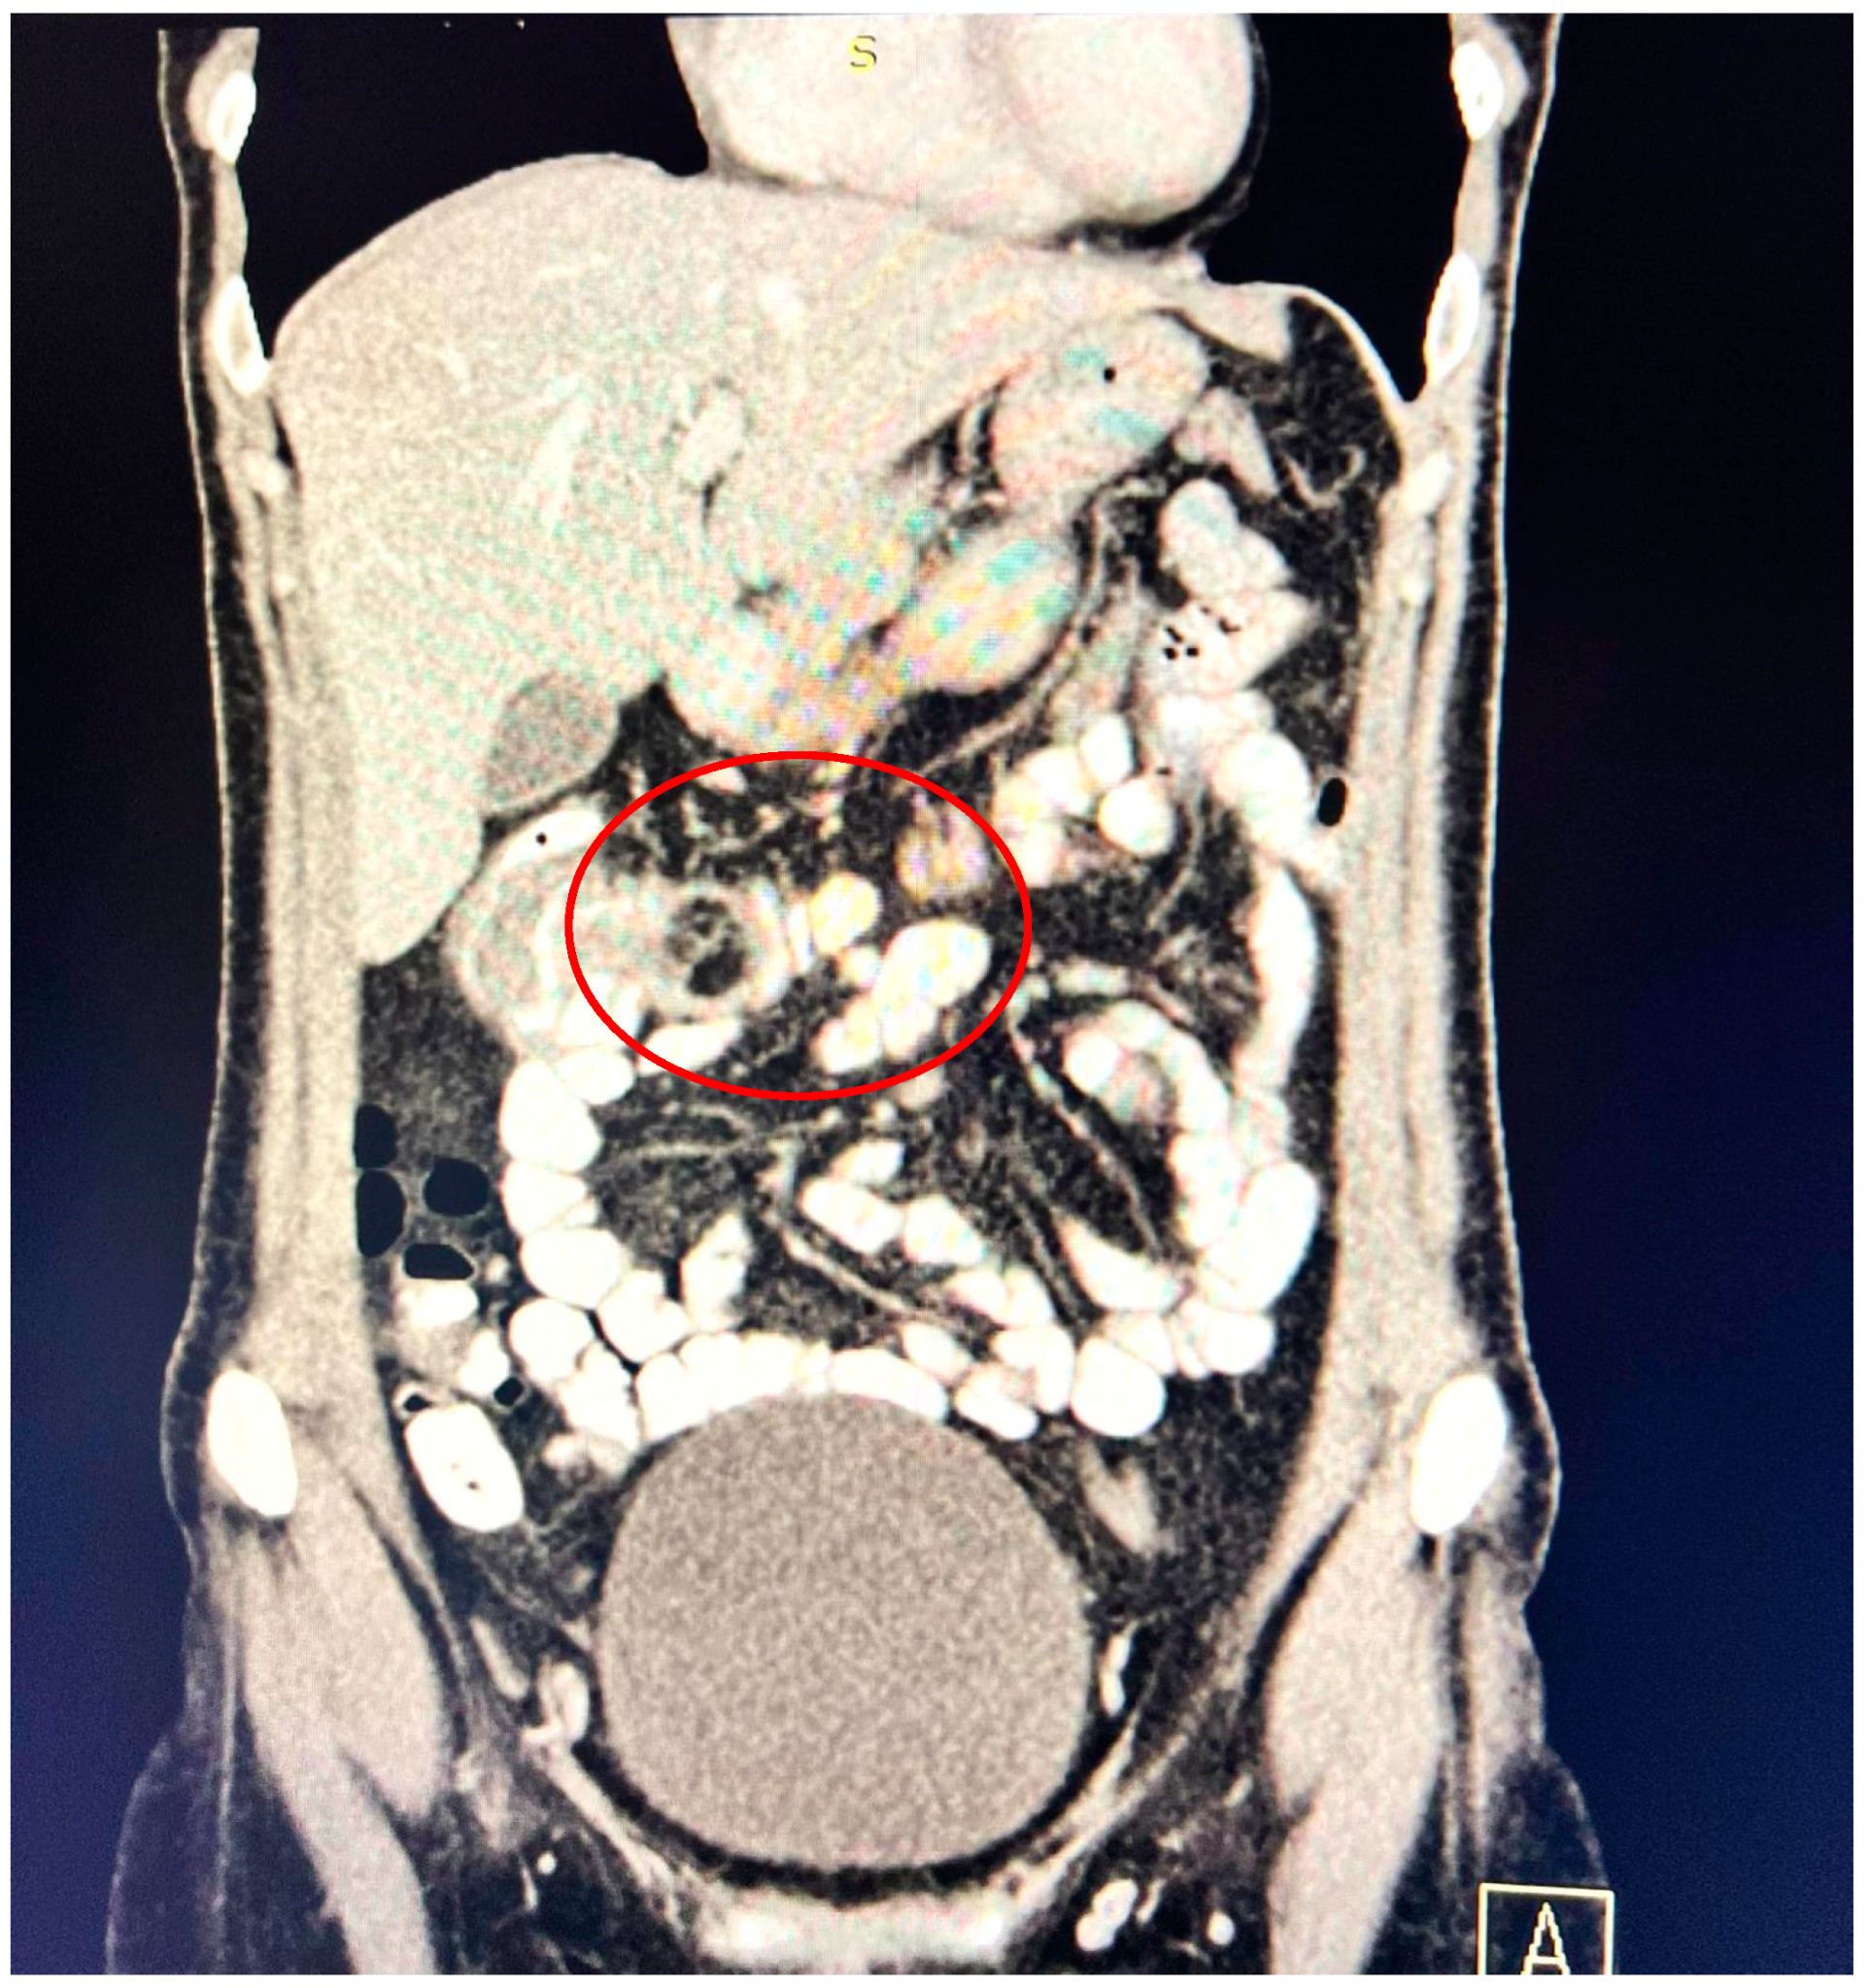

A contrast-enhanced computed tomography (CT) scan conducted on the day of admission revealed circumferential parietal thickening of a maximum of 21 mm at the hepatic flexure of the colon. This thickening extended over a length of approximately 45 mm, resulting in filiform, axial stenosis of the lumen, without any overlying distension of the colonic frame. The parietal thickening was moderately iodophilic and accompanied by discrete linear-type densification of locoregional fat, which was most likely a desmoplastic reaction. A tumor formation with a maximum axial diameter of approximately 29/28 mm, extending craniocaudal on a length of approximately 27 mm, was located at the distal end of the parietal ingrowth with an intraluminal site. This tumor formation had a polycyclic contour, thin septa within, and a discrete lodophilic peripheral appearance. It appeared to have a wide base of implantation at the level of the postero-inferior wall of the colon; mild hepatomegaly in the liver, with a homogeneous structure and a regular surface, and the absence of focal primary or secondary lesions; adenopathies in the hepatic hilum with a maximum diameter of 16/12.5 mm and in the celio-mezenteric territory with a maximum diameter of 24/19 mm; microadenopathies with the gastro-hepatic ligament; and an absence of subdiaphragmatic fluid (Figure 1, Figure 2 and Figure 3).

Figure 1. Circumferential parietal thickening noted at the hepatic flexure of the colon measuring 21/45 mm, moderately iodophilic, associated with discrete linear-type densification of locoregional fat, indicative of a desmoplastic reaction.

Figure 2. Intralumenal mass with an axial diameter of 29/28 mm and extended cranio-caudally over a length of 27 mm, showing polycyclic contour, discretely iodophilic peripherally.

Figure 3. Mass resulting in filiform axial narrowing of the lumen without associated distention of the colon.